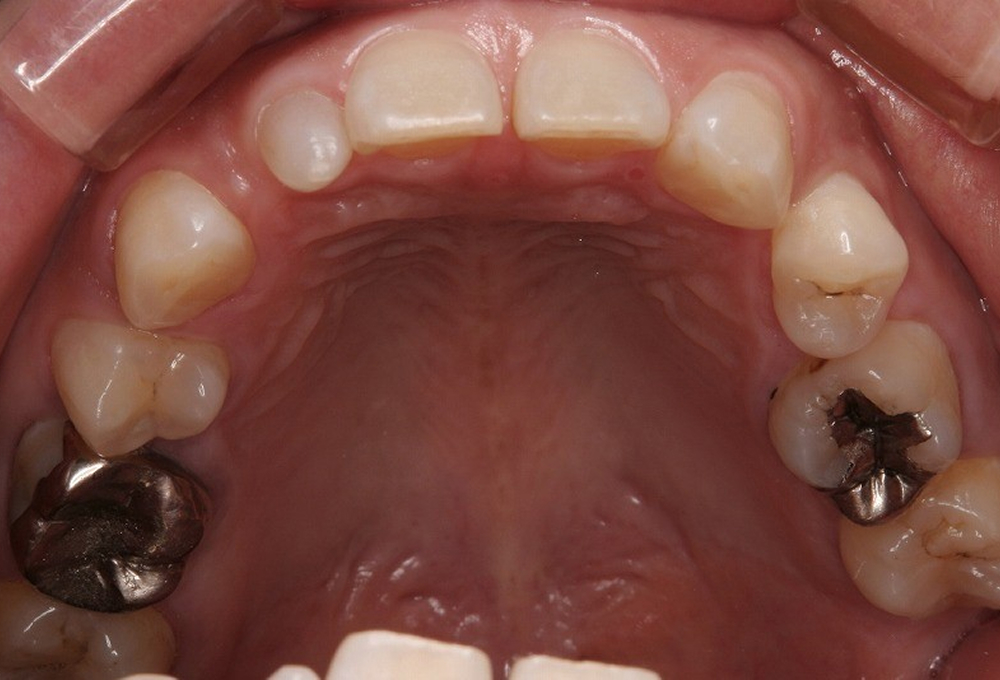

②術前上顎